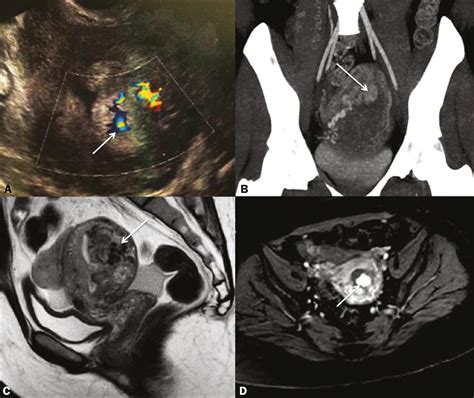

• Ultrasound to visualize the uterus and detect any retained placental fragments or other abnormalities

In some cases, additional imaging studies such as MRI may be recommended to get a more detailed view of the uterus.